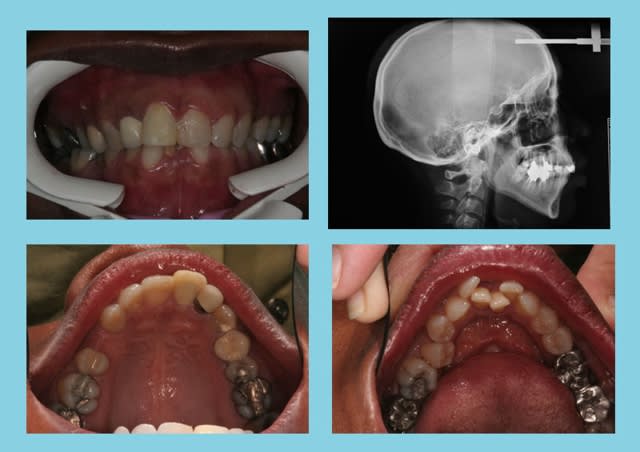

Sexe : F

Age 45 ans

Augmentation de longueur d’arcade = 15 mm.

Rien qu'à la PANO., on peut voir que les rapports 22/33 sont modifiés